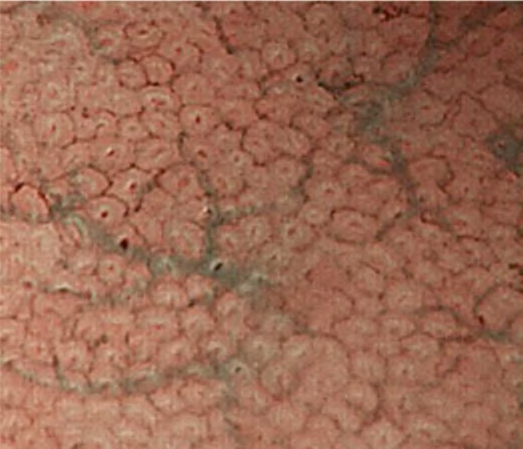

The VS classification system developed by the author (Kenshi Yao) [1] is the most widely accepted diagnostic system for magnifying narrowband imaging (M-NBI) of the stomach [2]. The VS classification system employs anatomical terms as endoscopic markers for analysis. Anatomical components visualized using M-NBI were divided into microvascular (MV) and microsurface (MS) patterns. As shown in . Fig. 1a–c, the subepithelial capillary and collecting venule were visualized for MV pattern, while the marginal crypt epithelium (MCE), crypt opening (CO), and intervening part (IP) between the crypts were identified for the MS pattern. In addition, in terms of the pathological status, the light blue crest [3] and white opaque substance [4] can be markers for microsurface patterns.

According to the morphology of the anatomical components, the MV and MS patterns were classified as regular, irregular, or absent (. Fig. 2). In principle, the MV and MS patterns must be determined separately.

DL is defined as the border between the lesion and non-lesion areas, discernible through an abrupt change in MV and/or MS patterns (. Fig. 2).